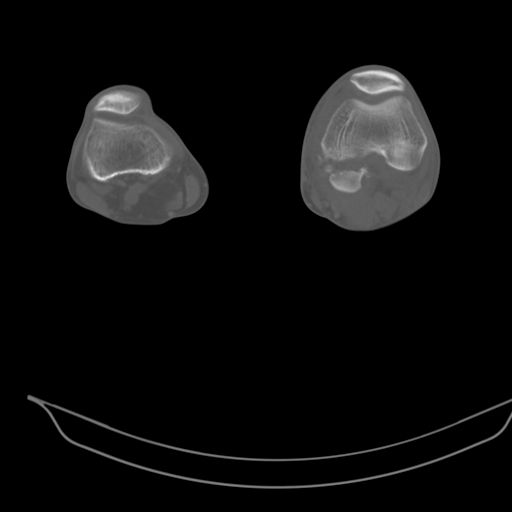

застарелый многооскольчатый перелом мыщелков бедра |

В клинику поступил больной 34 лет с закрытым многооскольчатым внутрисуставным переломом мыщелков левой бедренной кости со смещением.

Травма в шахте, 4 недели назад. Лечился в местной ЦРБ в гипсовой повязке. В области сустава была ссадина, которая на данный момент полностью зажила.

Сейчас в суставе сгибательная установка под углом 130*. Движения резко ограничены, болезнены. Больной направлен к нам для решения вопроса об эндопротезировании коленного сустава, однако мы не видим альтернативы артродезу.

Есть ли на ваш взгляд шанс избежать замыкания сустава у этого молодого и физически активного пациента?